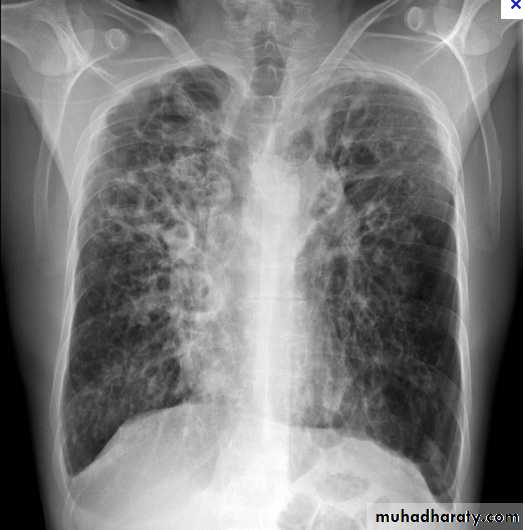

Miliary Tuberculosis. A cone-down view of a frontal radiograph demonstrates innumerable micronodular opacities characteristic of micronodular (miliary)

interstitial disease.

Transbronchial biopsy demonstrated caseating granulomas containing acid-fast bacilli.

Miliary TB

a frontal radiograph demonstrates innumerable micronodular opacities characteristic of micronodular (miliary) interstitial disease. Transbronchial biopsy demonstrated caseating granulomas containing acid-fast bacilli.